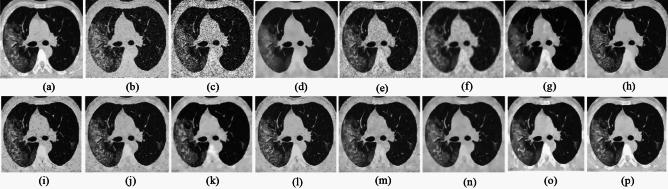

Medical imaging systems such as computed tomography (CT) and magnetic resonance imaging (MRI) are vital tools in clinical diagnosis and treatment planning. However, these modalities are inherently susceptible to Gaussian noise introduced during image acquisition, leading to degraded image quality and impaired visualization of critical anatomical structures. Effective denoising is therefore essential to enhance diagnostic accuracy while preserving fine details such as tissue textures and structural boundaries. This study proposes a robust and efficient denoising framework specifically designed for CT and MRI images corrupted by Gaussian noise. The method integrates a cluster-wise principal component analysis (PCA) thresholding approach guided by the Marchenko-Pastur (MP) law from random matrix theory and a non-local means algorithm. Noise level estimation is achieved globally by analysing the statistical distribution of eigenvalues from noisy image patch matrices and leveraging the MP law to accurately determine the Gaussian noise variance. An adaptive clustering technique is employed to group similar patches based on underlying features such as textures and edges and enables localized denoising operations tailored to heterogeneous image regions. Within each cluster denoising is performed in two stages where initially hard thresholding based on the MP law is applied to the singular values in the SVD domain to obtain a low-rank approximation that preserves essential image content while removing noise-dominated components. Residual noise in the low-rank matrix is then further suppressed through a coefficient-wise linear minimum mean square error LMMSE estimator in the PCA transform domain. Finally, a non-local means algorithm refines the denoised image by computing weighted averages of pixel intensities and prioritizing neighbourhood similarity over spatial proximity to effectively preserve edges and textures while reducing Gaussian noise. Experimental evaluations on CT and MRI datasets demonstrate that the proposed method achieves superior denoising performance while maintaining high structural similarity and perceptual quality compared to existing state-of-the-art approaches. The method demonstrates adaptability noise reduction capability and preservation of anatomical detail that make it well suited for precision critical medical imaging applications.

计算机断层扫描(CT)和磁共振成像(MRI)等医学成像系统是临床诊断和治疗规划中的重要工具。然而,这些模态在图像采集过程中固有地容易受到高斯噪声的影响,导致图像质量下降以及关键解剖结构的可视化受损。因此,有效的去噪对于提高诊断准确性同时保留诸如组织纹理和结构边界等精细细节至关重要。本研究提出了一种强大且高效的去噪框架,专门针对受高斯噪声破坏的CT和MRI图像设计。该方法集成了一种由随机矩阵理论中的马尔琴科 - 帕斯图尔(MP)定律引导的聚类主成分分析(PCA)阈值处理方法和一种非局部均值算法。通过分析噪声图像块矩阵的特征值统计分布并利用MP定律来准确确定高斯噪声方差,实现全局噪声水平估计。采用自适应聚类技术根据纹理和边缘等潜在特征对相似块进行分组,并针对异质图像区域进行局部去噪操作。在每个聚类中,去噪分两个阶段进行,首先在奇异值分解(SVD)域中基于MP定律应用硬阈值处理奇异值,以获得保留基本图像内容同时去除噪声主导成分的低秩近似。然后在PCA变换域中通过系数线性最小均方误差(LMMSE)估计器进一步抑制低秩矩阵中的残余噪声。最后,非局部均值算法通过计算像素强度的加权平均值并优先考虑邻域相似性而非空间邻近性来细化去噪图像,从而在减少高斯噪声的同时有效保留边缘和纹理。对CT和MRI数据集的实验评估表明,与现有的最先进方法相比,所提出的方法在保持高结构相似性和感知质量的同时实现了卓越的去噪性能。该方法展示了适应性降噪能力和解剖细节保留能力,使其非常适合精密关键的医学成像应用。